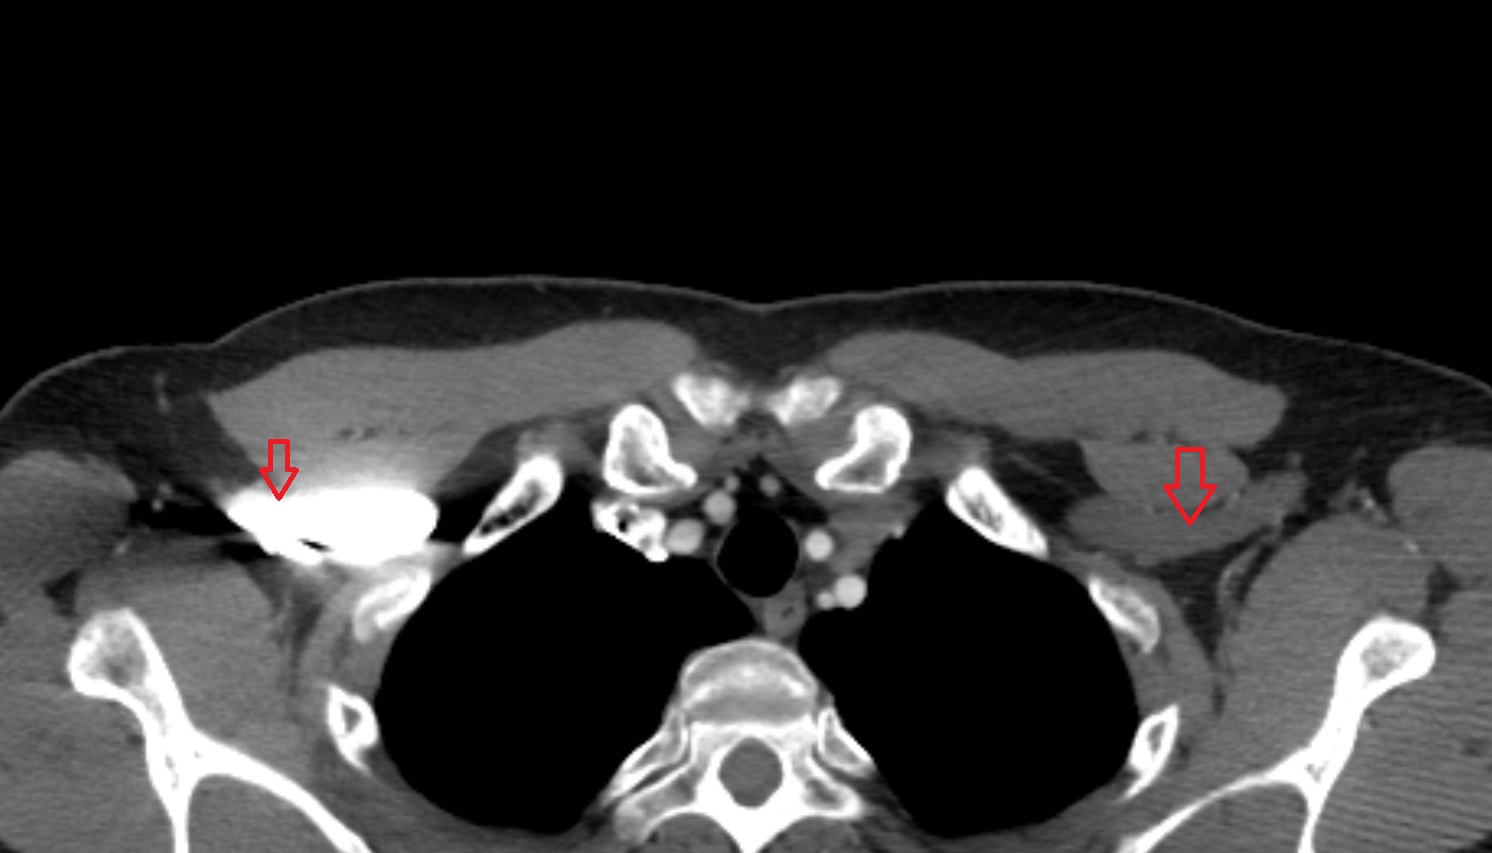

- Axillary lymph nodes

- Infraclavicular lymph nodes

- Left brachiocephalic vein

- Left subclavian vein

- Right subclavian vein

- Right brachiocephalic vein